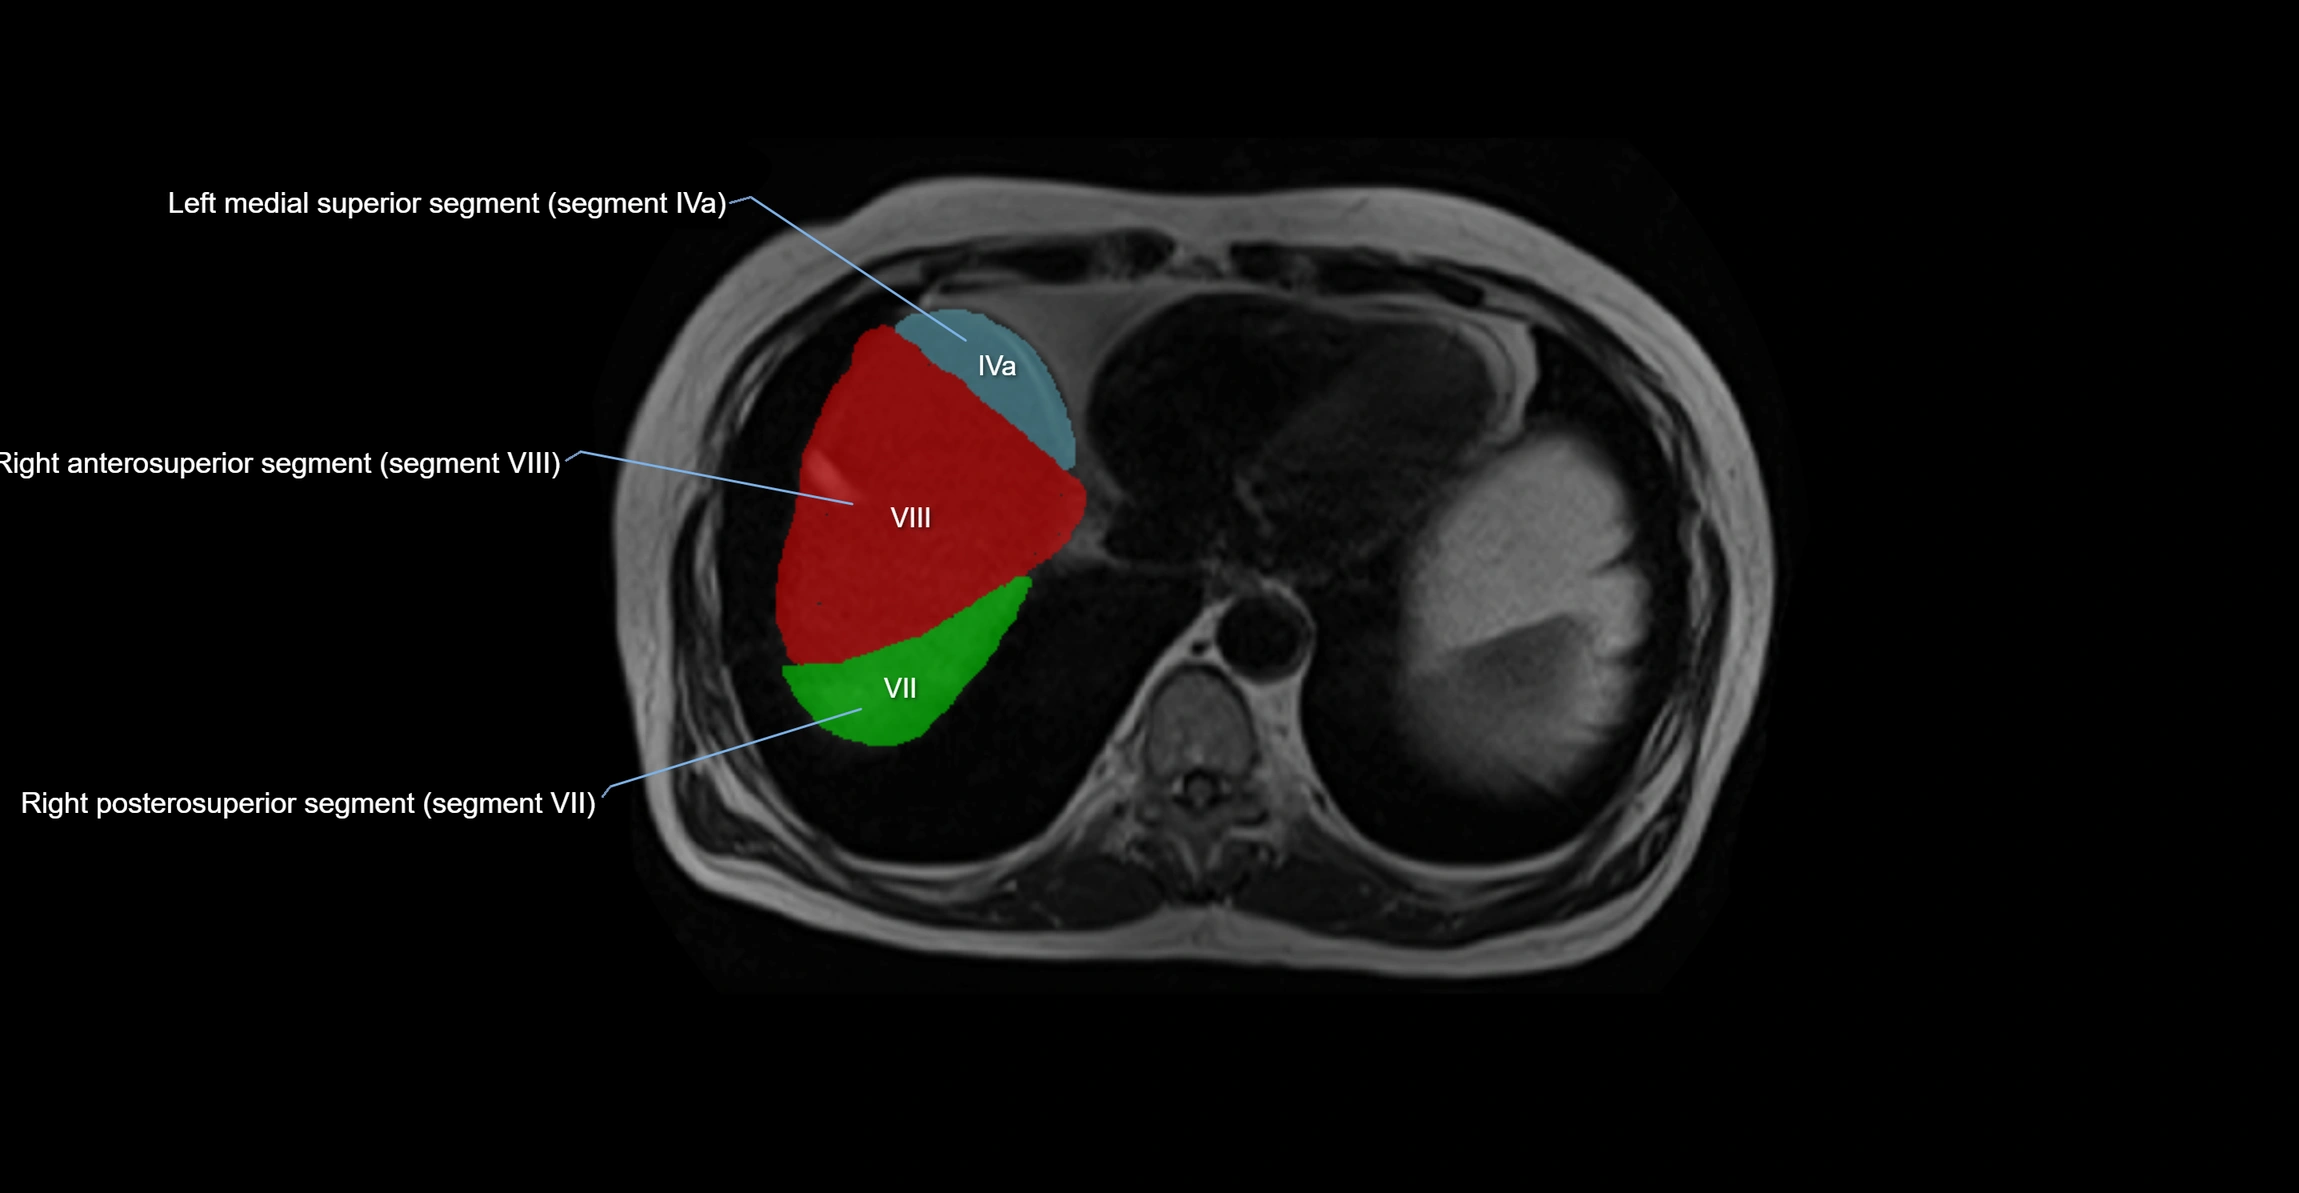

The caudate lobe of the liver is a distinct anatomical subdivision of the liver, designated as segment I in Couinaud’s classification. It lies on the posterior surface of the liver, between the fissure for the ligamentum venosum (left boundary) and the groove for the inferior vena cava (IVC) (right boundary). Superiorly, it is related to the posterior liver surface, and inferiorly it is separated from the left lobe by the porta hepatis.

The caudate lobe is unique because it receives dual portal venous and arterial inflow from both the right and left portal veins and hepatic arteries. It also has independent venous drainage directly into the IVC via multiple small hepatic veins, unlike other lobes that drain through the three main hepatic veins.

This anatomical autonomy makes the caudate lobe especially significant in liver surgery, transplantation, and hepatic venous outflow obstruction syndromes (e.g., Budd–Chiari syndrome). Enlargement of the caudate lobe is a characteristic imaging feature in chronic liver disease and cirrhosis.